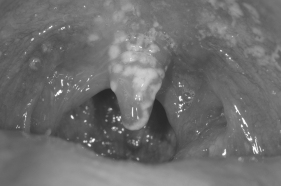

Infections of the Skin and Eye

Infections of the Respiratory Tract